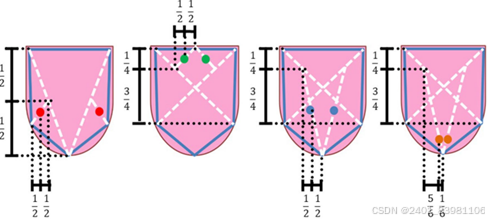

### 舌象特征提取:

1. **形状特征**:

- 轮廓提取:利用边缘检测算法获取舌部轮廓信息。

- 形状描述符:计算面积、周长、圆度等形状特征。

形质识别:现状:特殊如齿痕,腐腻等不能全面分析。针对齿痕、裂 纹等单一形质特征的研究较深入:

方法:借助深度学习3D RFCR网络模型 、3D MeshCNN等模型有望实现三维舌象图像可视化表达,如双目立体视觉,结构光法